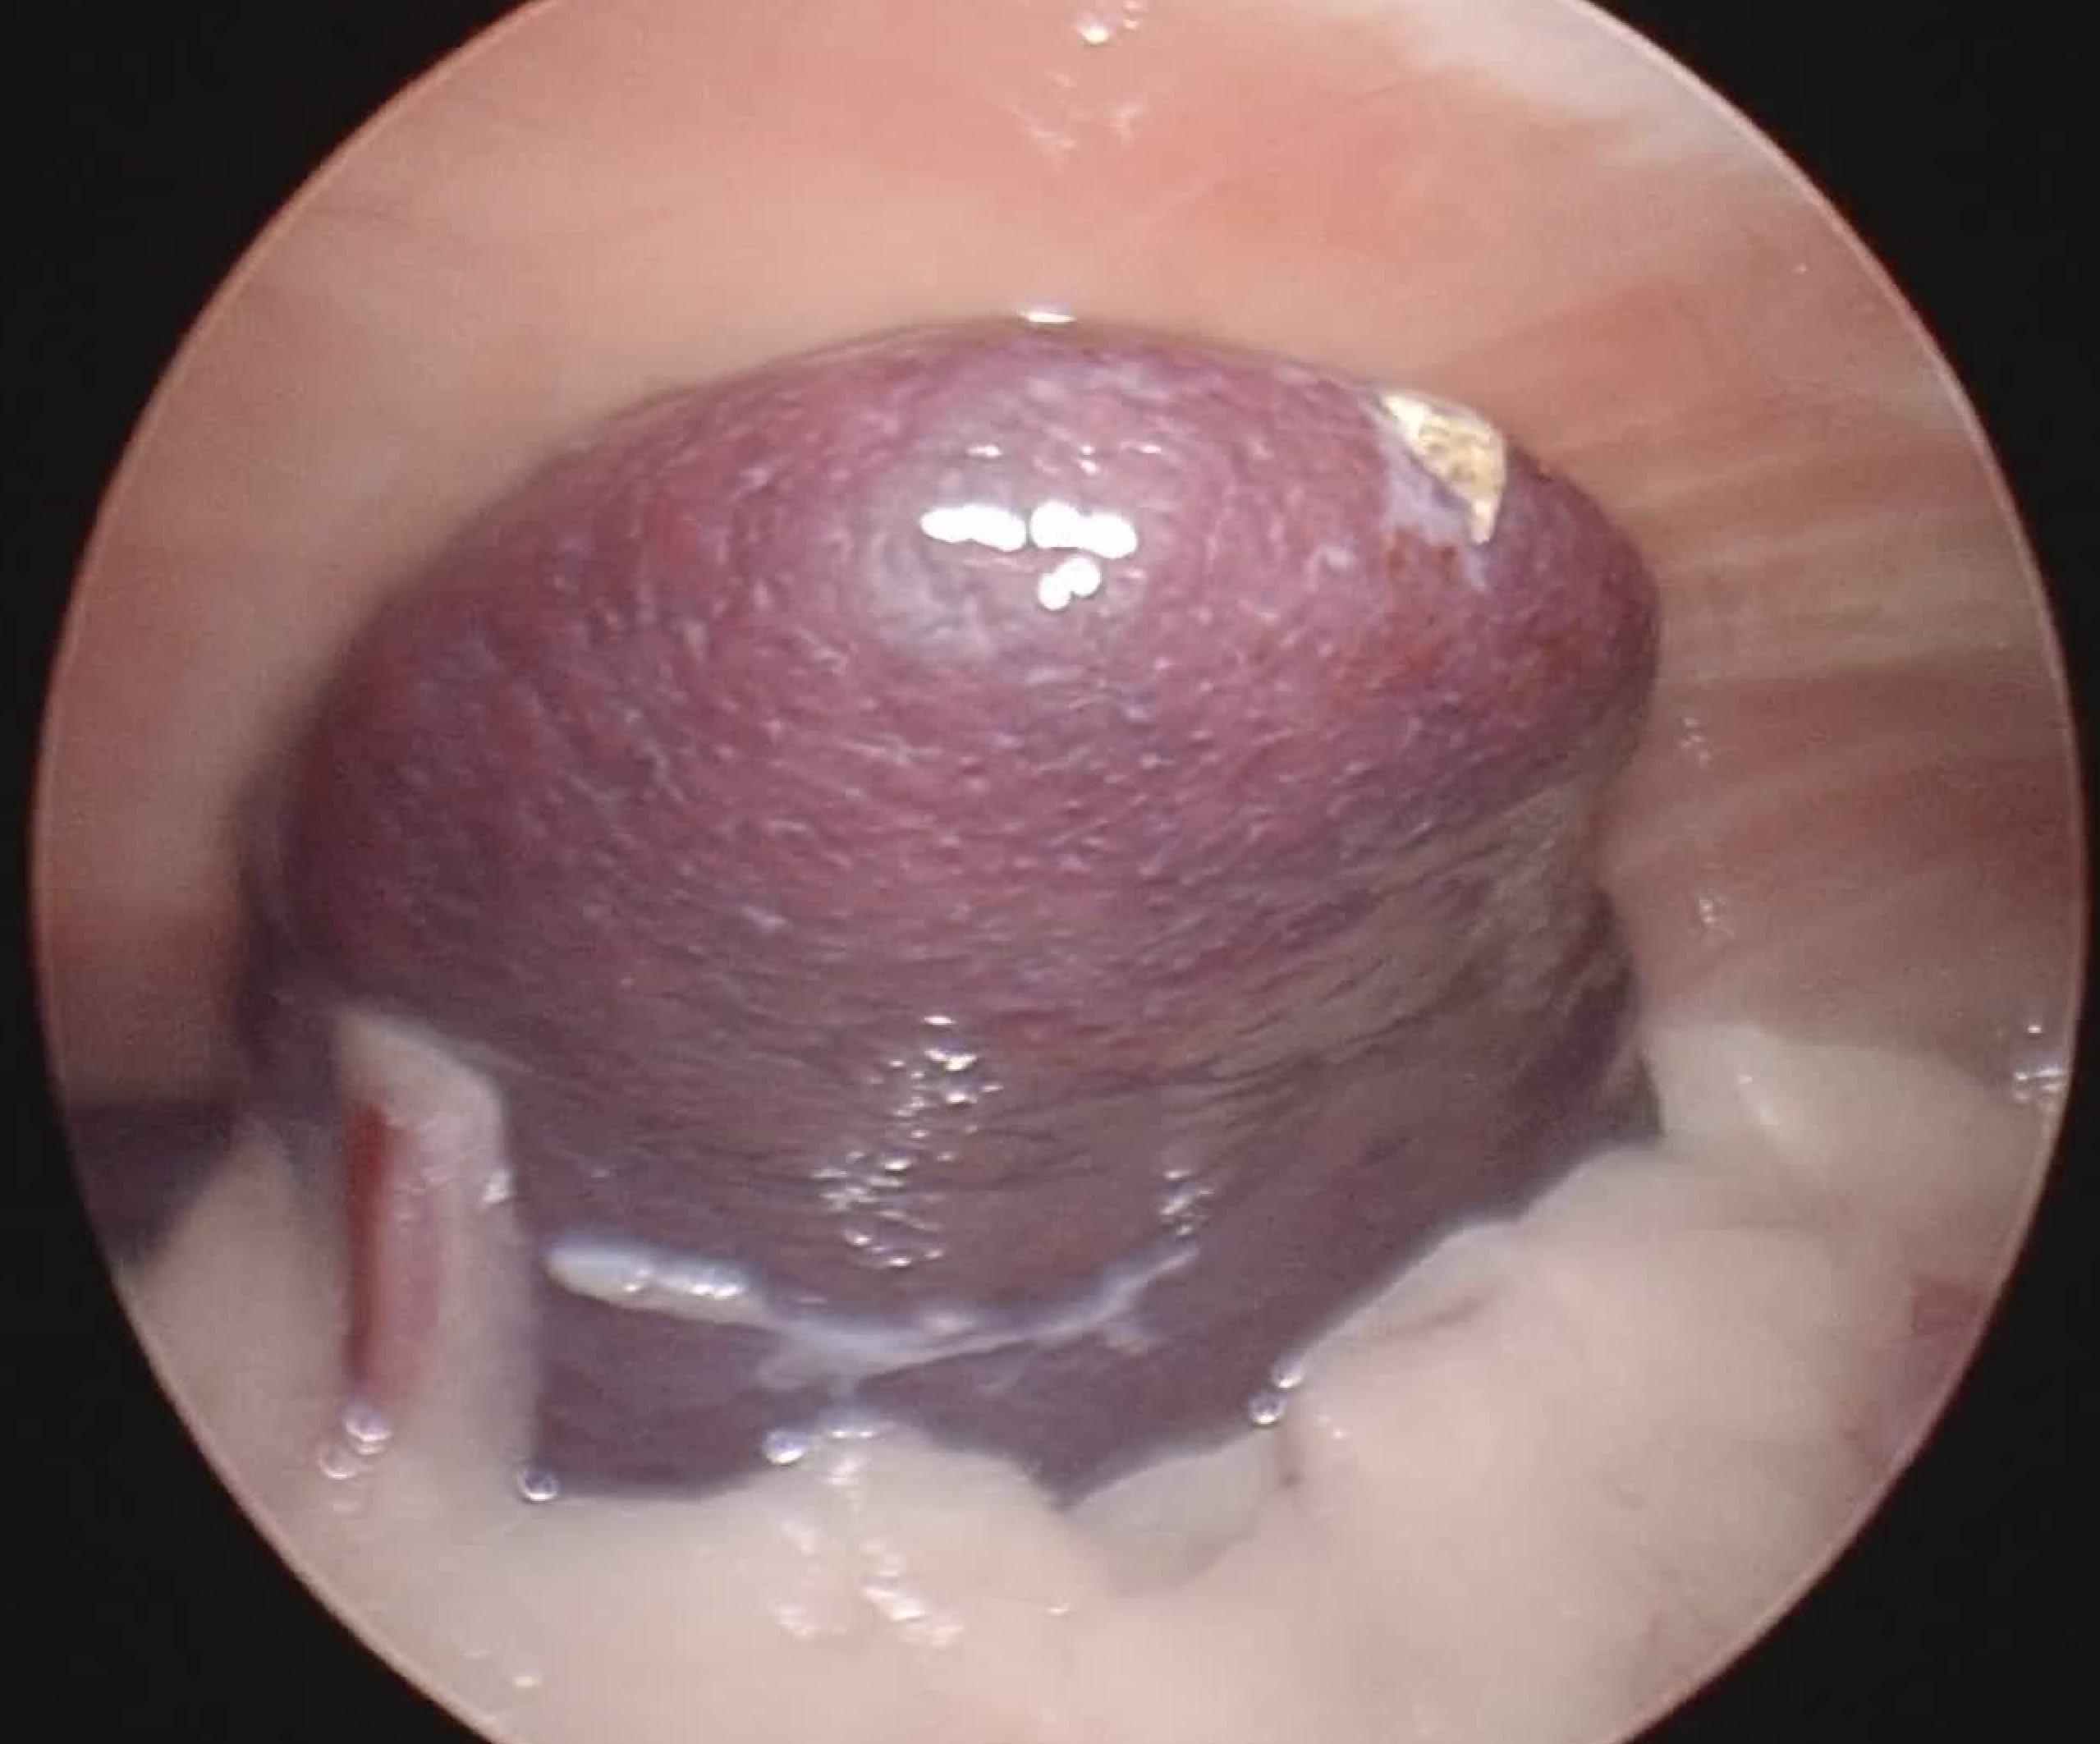

こちらは避妊手術の様子です。

1枚目の写真は脾臓を示していて、腹腔鏡を用いることで肝臓以外の胆嚢や脾臓など周辺の臓器の確認、出血の程度なども観察しながら手術を行うことが可能です。